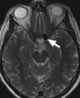

Parasellar signal void

May Be Caused by

Basilar tip aneurysm

Carotid-cavernous fistula

Cavernous carotid aneurysm

Densely calcified meningioma

Kissing carotids

Pneumatized posterior clinoid

Supraclinoid carotid aneurysm